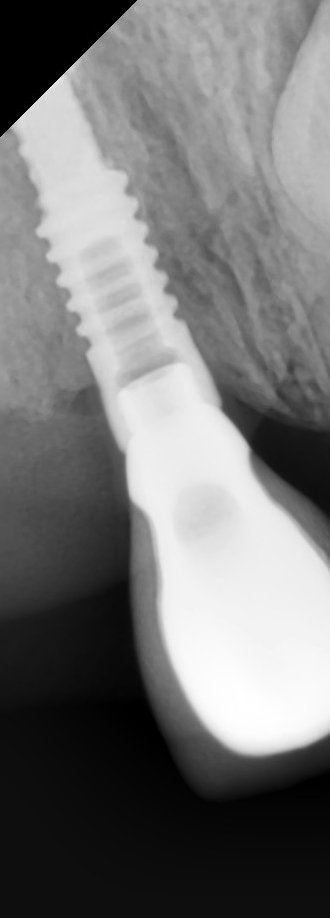

El paciente llega con estos implantes puestos en otra ciudad y sin coronas. Conexión interna. Podrian ayudarme para saber que implantes son?